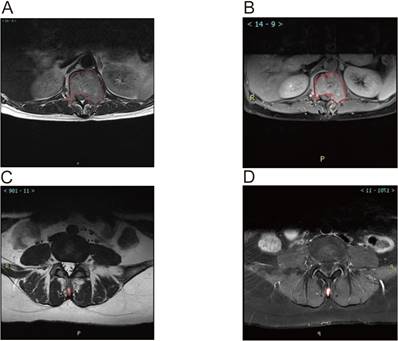

MRI analysis revealed significant associations between the ratio of high-intensity zones (RHI) and pain severity (Table 3). The median RHI was 47% (range: 10-84%). Patients with mild pain (VAS 1-3) exhibited a median RHI of 27% (range: 10-43%), whereas those with moderate pain (VAS 4-7) and severe pain (VAS 8-10) had significantly higher median RHIs of 59% (range: 32-78%) and 66% (range: 39-84%), respectively (P < 0.0001). Figure 3 illustrates representative MRI images showing the locations of metastatic lesions and associated high-intensity zones. Correlation analysis confirmed a significant linear relationship between RHI and pain scores (Figure 4).

Figure 3

Magnetic Resonance Imaging (MRI) Images showed Metastatic Lesion location and high-intensity zone in Patients With spine metastasis of breast cancer. A. Calulate the proportion of whole cord in the T2 scan image of the lumbar metastasis. B. Calulate the proportion of high indesity area in the T2 scan image of the lumbar metastasis. C. Calulate the proportion of whole cord in the T2 scan image of the Spinous process metastasis. D. Calulate the proportion of high indesity area in the T2 scan image of the Spinous process metastasis.